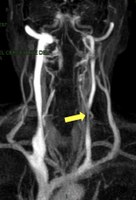

Risonanza Magnetica delle vene cerebrali. La freccia gialla dimostra un restringimento della vena giugulare interna, caratteristico della CCSVI